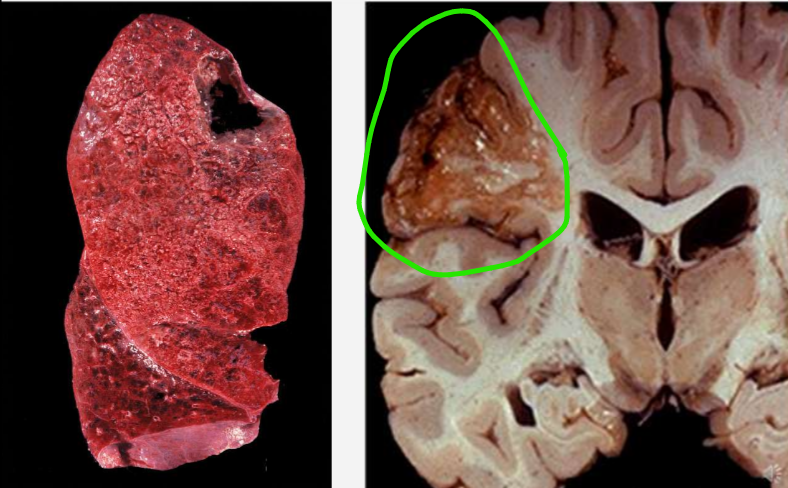

kas yra infarktas, dėl ko atsiranda

audinio nekrozė, kurią sukelia išemija

dėl kraujagyslės uzsikimšimo, O2 negavimas

kur ir kas vyskta koaguliacinėje nekrozėje

ten, kur gausu baltymų

denatūruojasi baltymai → audinys balkšvos spalvos

kas vyskta ląstelėje koaguliacinės nekrozės metu mikroskopiškai

kontūrai išlieka

branduolio nematyti

kaip atrodo makroskopiškai koaguliacinė nekrozė

audinys tvritas, kietas, sausas, pilkai gelsvas

aiški riba tarp pažeisto ir sveiko audinio

infarktas būna pleišto formos ir geltonas

koaguliacinės nekrozės pavyzdžiai

miokardo, insktų infarktas

daugiausiai širdyje ir inkstuose, blužnyje

kas ir kur vyskta kolikvacinės nekrozės metu, kas formuojama

audinys skystėja ir tirpsta

ten, kur lipidų yra

formuoja cistines ertmines struktūras

dėl ko vyskta smegenų infarktas, kokia nekrozė

dėl hipoksijos → koalikvacinė nekrozė